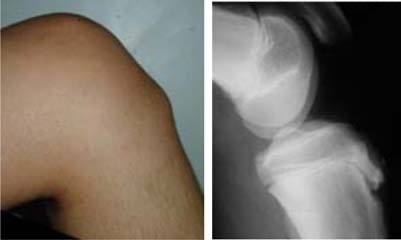

La malaltia d’Osgood - Schlatter és una de les causes més freqüents de dolor de genoll en el nen, especialment entre els 10 i els 15 anys, encara que també pot ocórrer a edats més primerenques. És més freqüent en els nens i nenes que fan esport.

La malaltia es caracteritza per un dolor que apareix en realitzar activitats físiques (caminar, córrer, saltar…), just per sota del genoll, en la part anterior. S'acompanya d'inflamació local i dolor important en tocar aquesta zona.

La causa bàsicament una sobrecàrrega mecànica en una zona de creixement de la tíbia. Aquesta és donada per estirades repetitives del tendó rotulià (que és el que uneix la ròtula a la tíbia), sobre una àrea de creixement que és relativament feble. Això pot provocar un fenomen inflamatori local com a resposta de reparació.